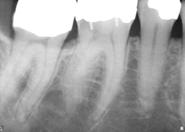

Radiografii

pungi parodontale de 4-6 mm

resorbtie osoasa

pungi parodontale > de 6 mm

resorbtie osoasa accentuata